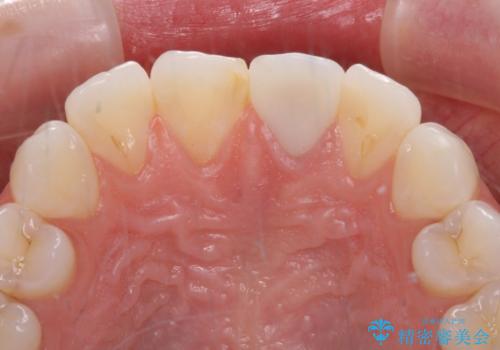

[セラミック治療] 前歯の見た目をきれいにしたい

![[セラミック治療] 前歯の見た目をきれいにしたいの症例 治療後](https://seimitsushinbi.jp/wp/wp-content/uploads/2021/06/06be0471d173ef54e4277b1c3034407c-500x350.jpg?v=1622871768)